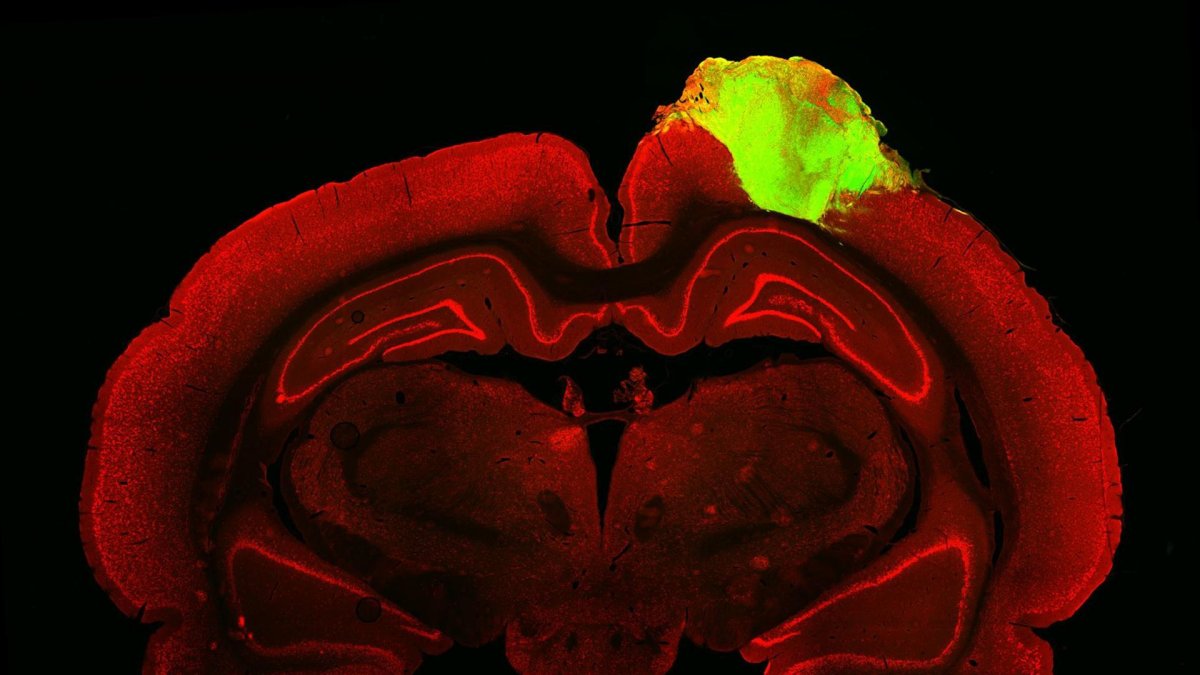

Imagen histológica de un cerebro de rata con un organoide cerebral humano injertado.

Un equipo de científicos ha demostrado que los organoides cerebrales humanos cultivados en laboratorio y trasplantados en cerebros de rata responden a estímulos visuales como luces intermitentes.

A los tres meses, los organoides injertados se habían integrado en el cerebro del huésped: se vascularizaron, crecieron, enviaron proyecciones neuronales y formaron sinapsis con las neuronas del huésped.

El equipo usó virus marcados con fluorescencia que saltan a lo largo de las sinapsis, de neurona a neurona, para observar las conexiones físicas entre el organoide y las células cerebrales de la rata huésped, así "pudimos rastrear las conexiones neuronales a partir de la retina del animal", explica Chen.